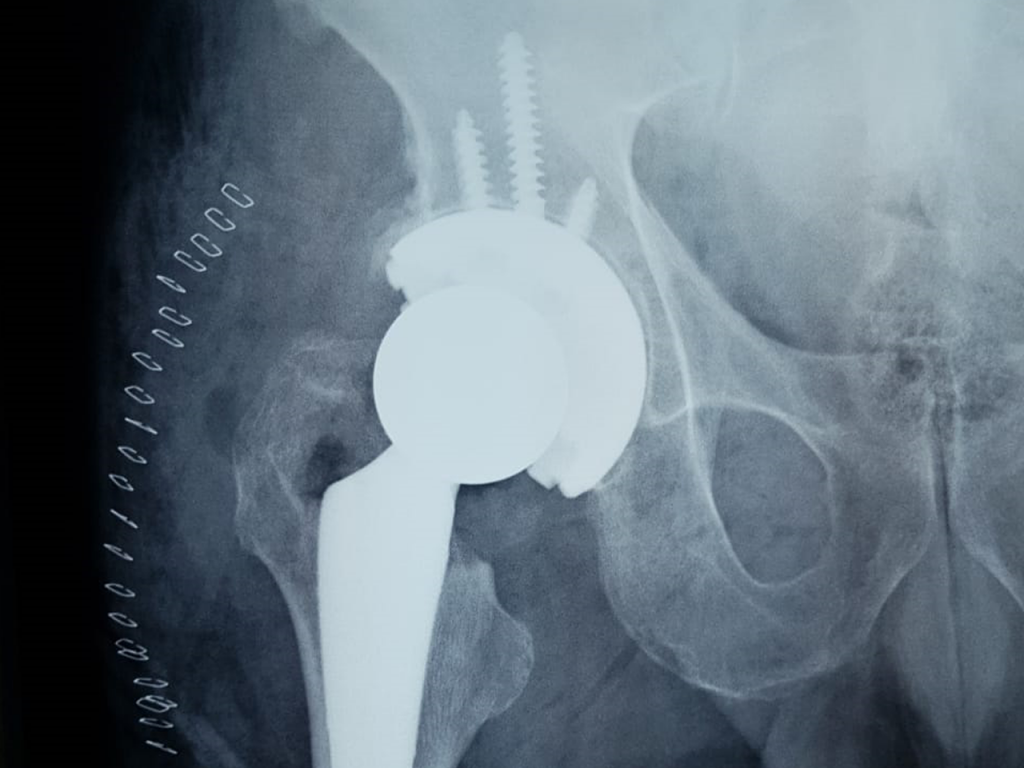

Remplazo Articular (protesis de rodilla y cadera)